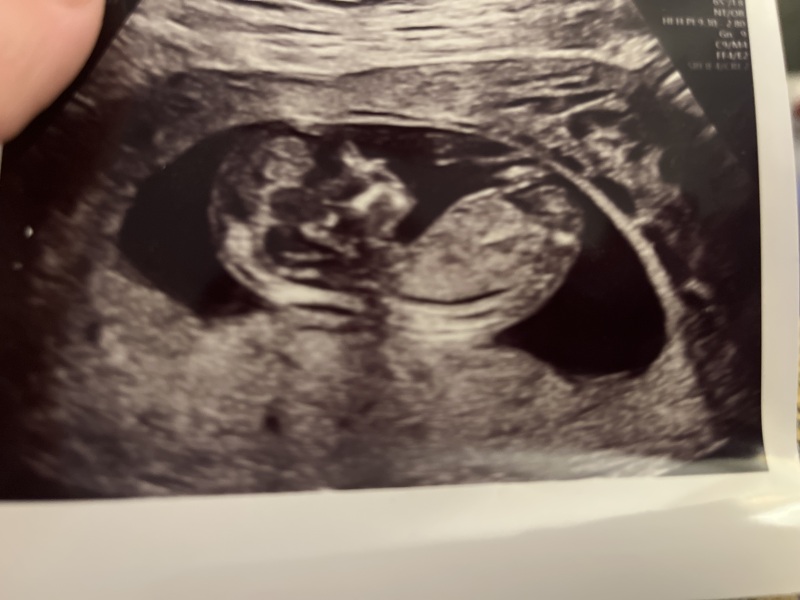

Hi all! We are expecting identical twins and are so excited to find out their gender. Here is a photo of the scan of twin 2. What does everybody think they could be using the nub theory? I know this isn’t accurate but it’s still fun to try and guess 😃

I’m going girl, been looking at loads recently trying to guess my own, using skull theory also, I think it’s a girl 😊